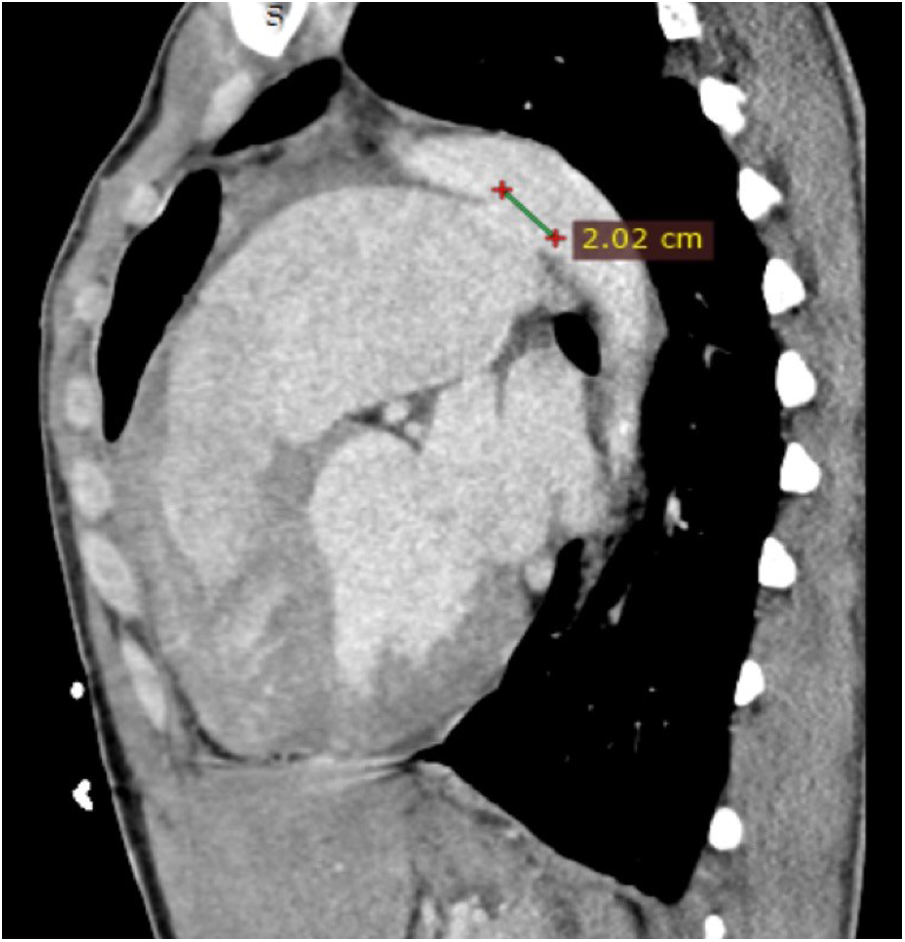

Transthoracic echocardiography (TTE) revealed severe left ventricular dilatation during diastole (73 mm) and an ejection fraction of 55%. Additionally, it showed that the patient has a bicuspid aortic valve with moderate aortic regurgitation (AR), as well as a mildly dilated ascending aorta (38 mm). Furthermore, the echocardiography indicated the presence of PDA, severe pulmonary valve regurgitation, and a significant enlargement of the pulmonary artery (73 mm). Following contrast-enhanced computed tomography (CT), it was found that the patient has a 20.2 mm PDA (Figure 1), which originates from the descending aorta, and 7 mm distal to the orifice of the left subclavian artery (LSA). According to the Krichenko classification, the PDA was classified as type B, which refers to a large duct with a short window-like structure at the aortic insertion (7).

Figure 1. Cardiac CT in sagittal view shows a large PDA (20.2 mm) with a dilated pulmonary artery. CT, computed tomography; PDA, patent ductus arteriosus.